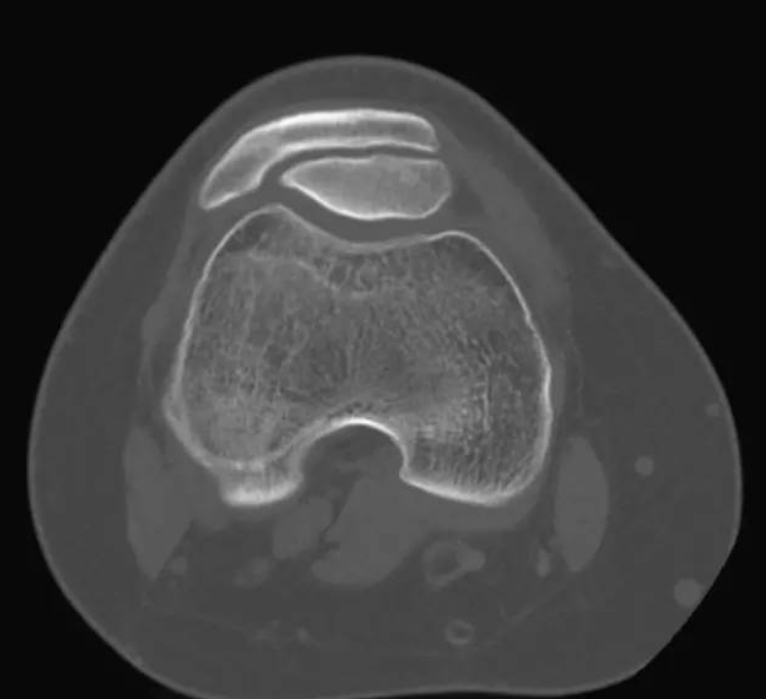

你见过“双层”的髌骨吗?